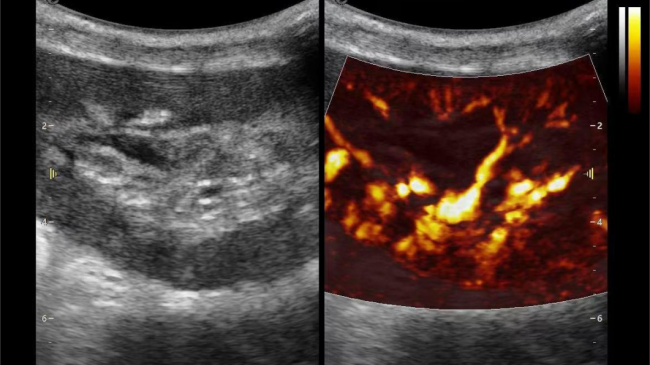

在肾移植领域,医生最怕的不是手术刀下的惊心动魄,而是那些手术后肉眼看不见的危机——急性排斥反应导致的血小板聚集形成的微血栓、毛细血管网损伤等...这些“隐形杀手”曾让无数移植肾在悄无声息中衰竭。而3377体育医疗(ESI)的iPlane Vascular平面波超微细血流显像技术,正是为破解这一难题而生。

微米级超高分辨率血流信号显像

这一项无创、无辐射操作简便且无需造影剂的黑科技,相当于用"高速摄像机"记录血液细胞的运动轨迹,让血管并发症"无处遁形。